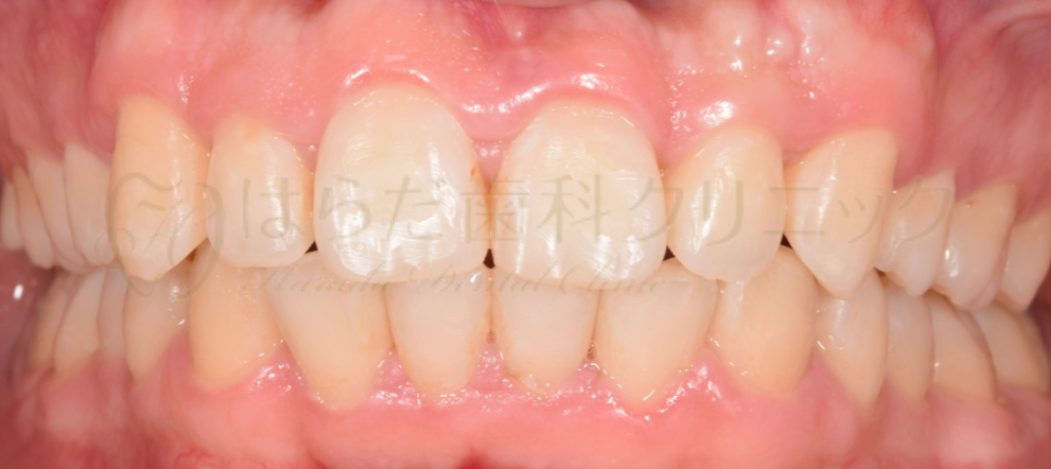

After

治療内容

舌側矯正

スペースを確保するため上下左右4番目を抜歯いたしました。

その後、全体的に歯の裏にて矯正をいたしました。

今回使用した矯正装置はメタルブラケットになります。

治療期間

約3年7か月

通院回数

35回